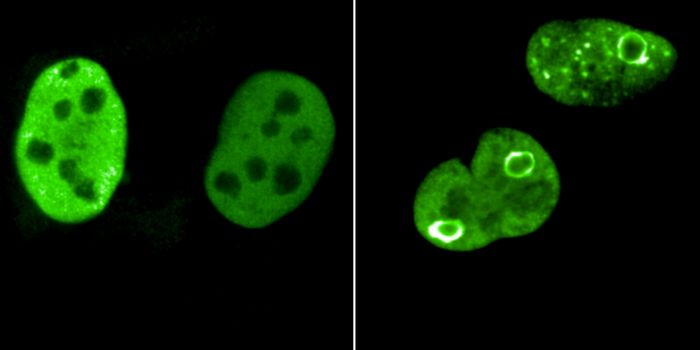

FEB 21, 2023Cell & Molecular BiologyThe Griffith Lab at UNC discovered telomeric protein & potential biomarker VR (green), shown in the nuclei (blue) of hum ...